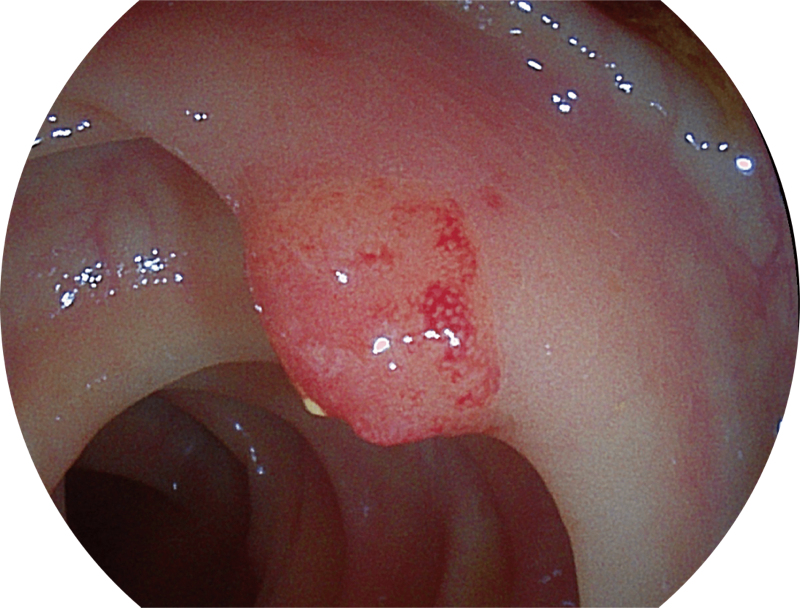

(Spectral Focused lmaging, SFI)

能够凸显黏膜浅层和中层血管轮廓,适用于中、远景观察下的病灶识别和早癌筛查。